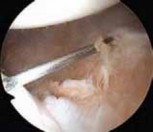

The surgical approach begins with the establishment of a standard posterior viewing portal, placed approximately 2 cm inferior and 1 cm medial to the posterolateral corner of the acromion. Upon entering the joint, a meticulous diagnostic sweep is performed. The surgeon must systematically evaluate the biceps anchor, the superior labrum, the articular surfaces of the humerus and glenoid, the rotator cuff footprint, and the entire capsulolabral complex. Particular attention is directed to the anteroinferior quadrant to confirm the presence of a Bankart or ALPSA lesion. The size and depth of any Hill-Sachs lesion are evaluated dynamically by taking the arm through a range of motion to assess for "engagement" over the anterior glenoid track.